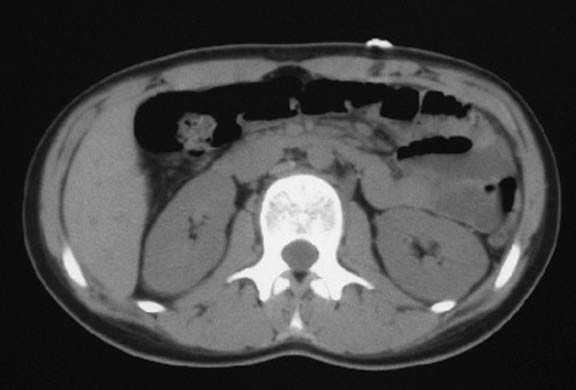

Aporta diverses exploracions complementàries: una ecografia abdominal, una ecografia ginecològica, una ecografia musculoesquelètica, un TAC abdominal, una gammagrafia òssia, una RMN i una anàlisi sanguínia. En el TAC abdominal es veu una imatge patològica al múscul recte de l'abdomen esquerre, compatible amb una cicatriu muscular (fig. 1). En l'ecografia ginecològica s'observa un quist fol·licular a l'ovari dret, al qual el ginecòleg no donà importància. En l'ecografia musculotendinosa es veuen dues cicatrius fibroses al múscul recte de l'abdomen esquerre a nivell diferent (fig. 2).

Figura 1